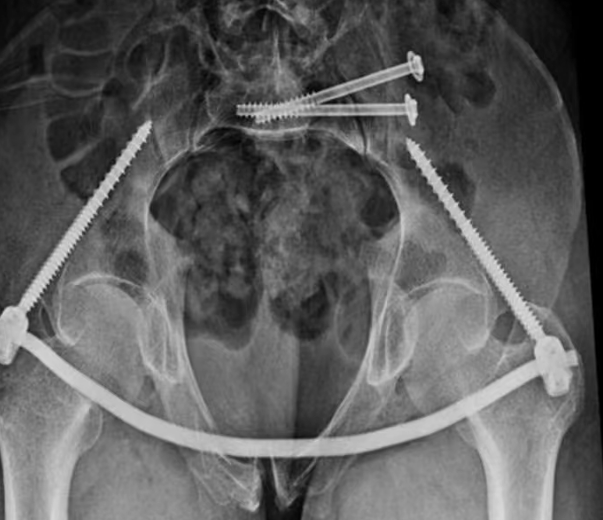

患者入院后,完善相关检查,诊断为:1.骨盆骨折(前后环损伤)2.右侧第1后肋、8-10前肋骨折 3.腰2左侧横突骨折。

李东柱副主任医师带领付开封,郭强医师立即制定详细手术方案,在麻醉科配合下,应用骨科机器人行骨盆后环第1、2骶髂关节螺钉固定+前环Infix内固定,手术顺利,术后护理团队精心照护,手术成功,尽最大努力实现了骨盆完美复位及精准螺钉置入、固定。

术后患者复查拍片骨折复位及固定良好,患者自我感觉良好,疼痛大大缓解,在床上可以随意翻身及坐起活动,约术后6-8周即可下地活动。术后给予进行指导康复,患者进行积极功能康复,待骨折愈合以后,肯定会有一个良好的功能。